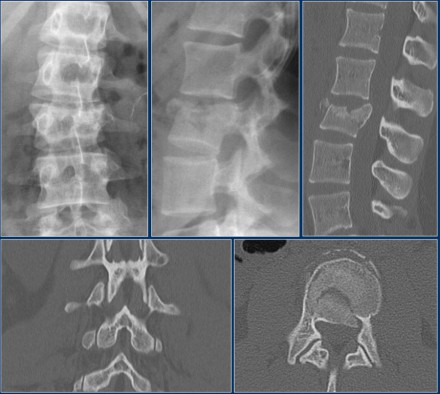

The images are of a patient with a typical bamboo spine as a result of ankylosing spondylitis.

After a fall on his back no fracture was seen on the x-rays.

However the CT shows a thin fracture line through the anterior side of the vertebral body and also through the spinous process.